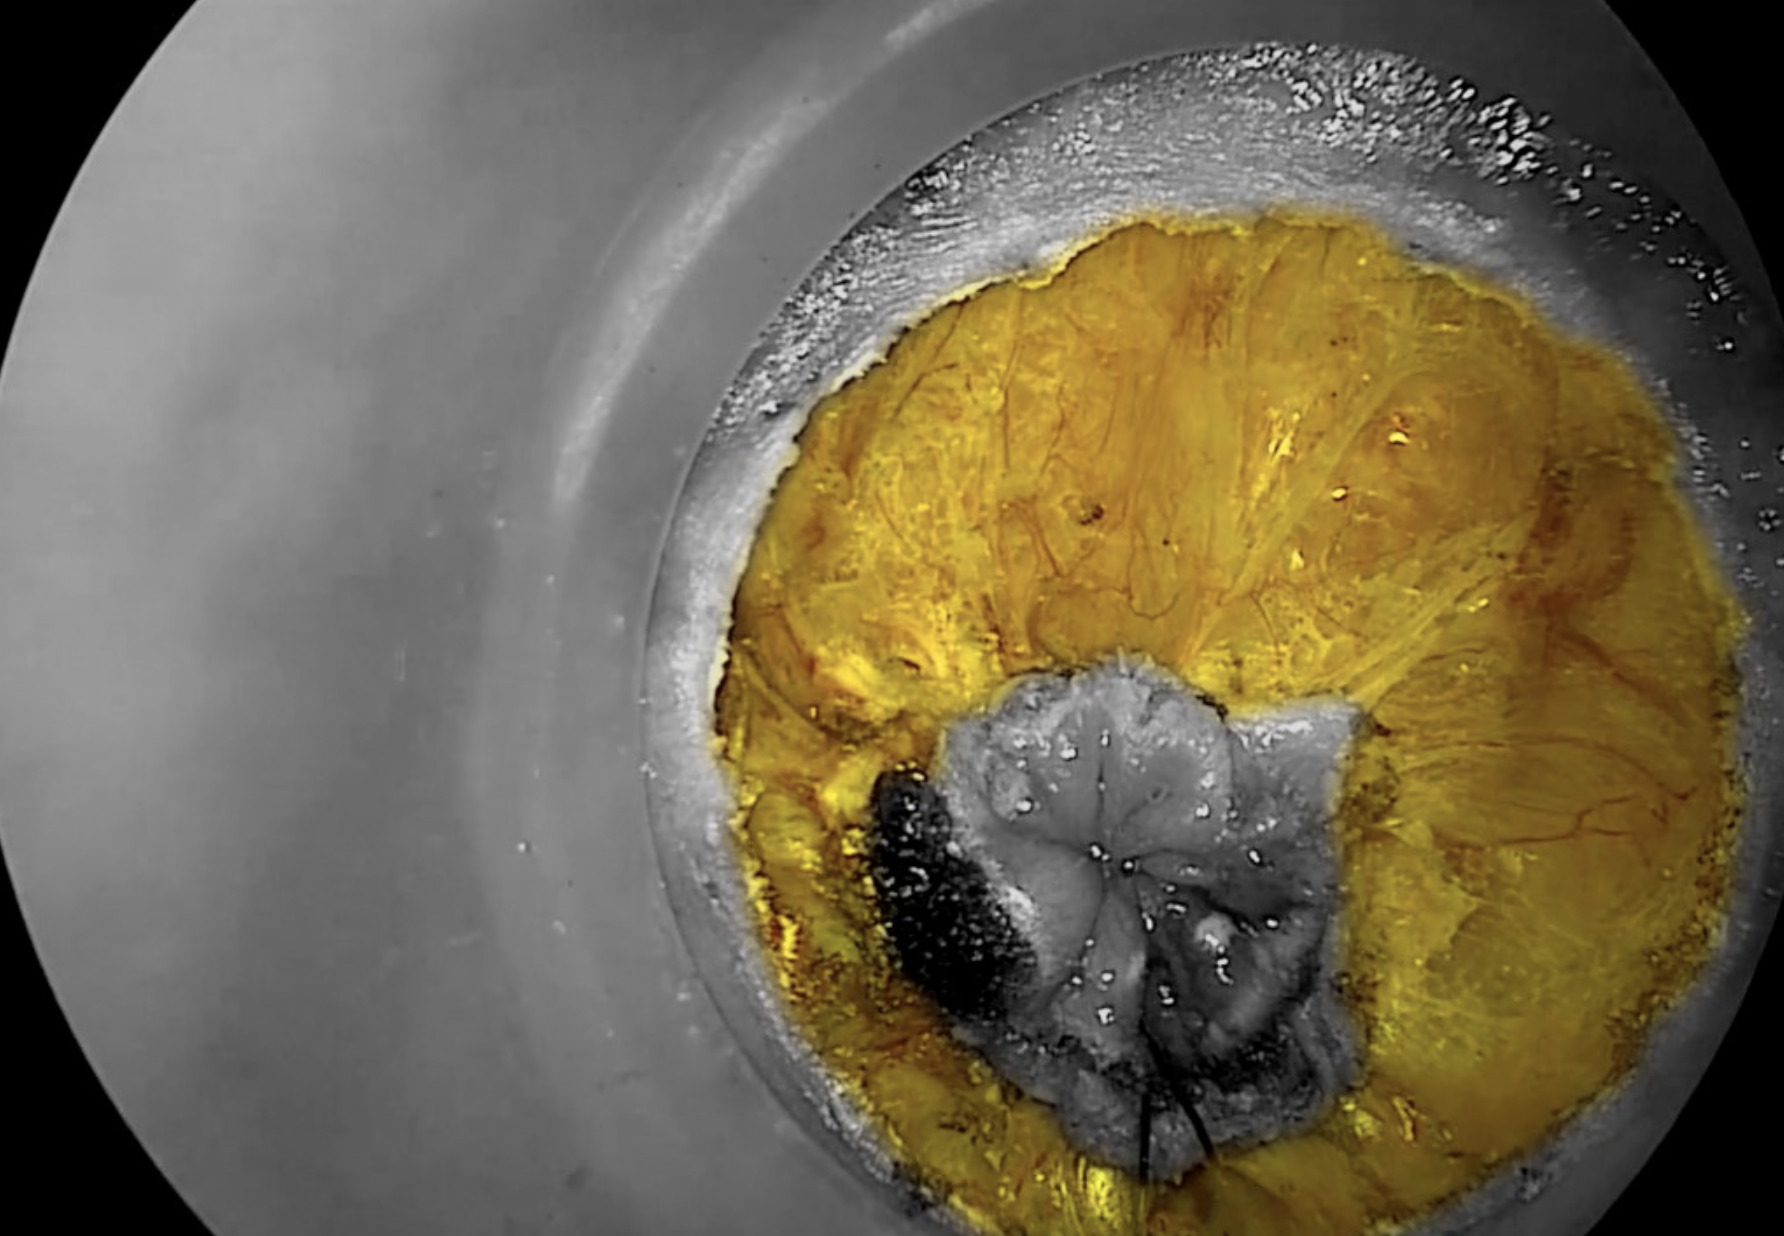

Using the hook diathermy, a full thickness incision of the entire rectal wall is completed.

Copyright Dr. Joep Knol

Diathermy hook dissection of the mesorectum, with yellow contrast showing entry into the correct mesorectal plane.

Circumferential entry into the correct mesorectal plane, highlighted in yellow.

The dissection proceeds in a standardized manner. Starting posteriorly, dissection is carried out perpendicularly through the rectal wall to the mesorectal fascia.